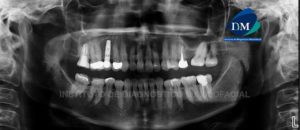

Paciente de sexo masculino 26 años de edad acude al Instituto de Diagnóstico de Maxilofacial para control post tratamiento. A la evaluación de la radiografía